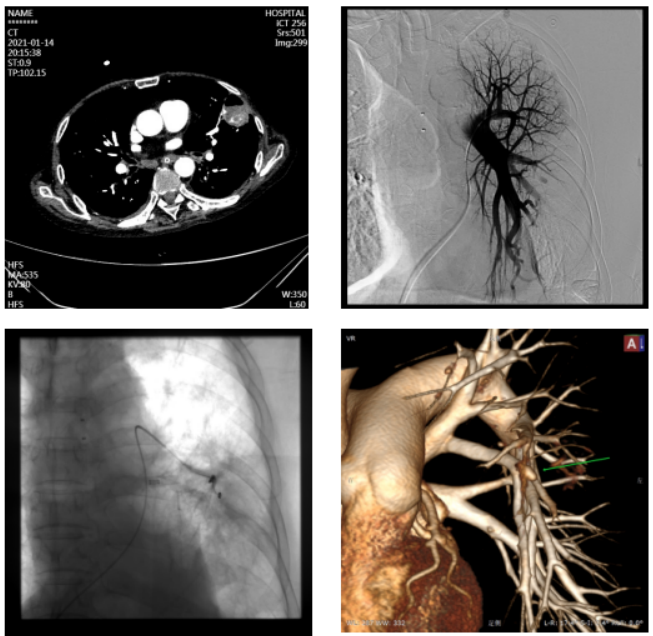

获得性PAPs的常⻅原因是创伤(通常为医源性)、感染、⾎管炎(特别是⽩塞病)和肿瘤。2017年发表的一篇文献纳入了24例患者,分析发现导致这些患者出现PAPs的主要原因包括感染、创伤、肿瘤、肺栓塞、支气管扩张、肺纤维化及特发性原因[4]。图源:AJR Am J Roentgenol, 2017, 208(1):84-91.从CT来看,PAPs可以分为中央型和外周型两种。中央型PAPs位于肺动脉干,定义肺动脉干直径29 mm或右叶间动脉直径17 mm,它们常与肺动脉高压有关。外周型PAPs位于肺内动脉上,很容易遗漏。由于急诊大咯血通常会行CT增强检查,然后再行支气管动脉栓塞,尤其在急诊情况下,可能会遗漏PAPs,进而出现危及生命的大咯血。越是远端血管越容易出现此种情况,因为远端血管壁较薄,而且被破坏。图源:Br J Radiol, 2017, 90(1073):20160783.图为一例53岁男性患者,因Swan-Ganz导管术诱发肺动脉假性动脉瘤(PAP):轴向CT血管成像(a,c),冠状重建(b)和三维重建(d)显示左上叶心尖段PAP(箭头)。患者接受保守治疗,病情稳定[5]。外周型PAPs造影分型:A型,肺动脉主干造影可见;B型,在肺动脉主干不可见,仅在选择性肺血管造影中可见;C型,支气管动脉造影可见,肺动脉造影不可见;D型,仅在肺CT血管造影可见,支气管动脉和肺动脉造影均不可见[6]。图源:Radiology, 2010 , 256(2):656-664.患者男性,70岁,入我院诊治,诊断为慢性阻塞性肺疾病(慢阻肺)、左⾆叶肺脓肿并PAPs、糖尿病。突发⼤咯⾎,⽓管插管。经抢救暂时止血。CT增强扫描发现血管膨大,肺动脉造影在肺动脉主干处发现PAP。CT容积重建技术(VR)也可见肺动脉瘤,其与肺动脉沟通。放置弹簧圈后⽌⾎。由于年龄较大,基础情况不佳,且有糖尿病、慢阻肺等合并症,患者于止血后半年余因肠穿孔死亡。